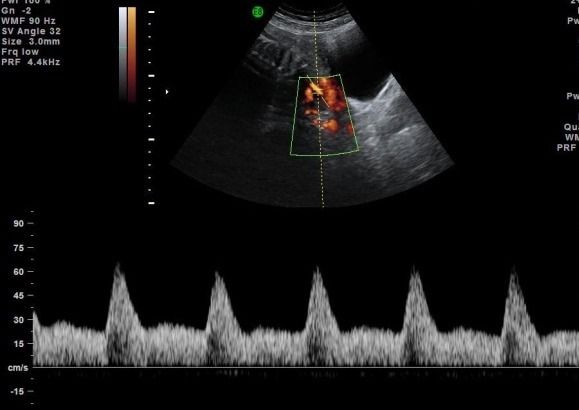

這個發現,在這幾年間不斷地被許多的國際期刊論文所引用,在接續的研究當中也發現,合併應用PlGF指數與超音波子宮動脈血流之檢測,可以有效在早期發現會發生子癲前症的孕婦群。

超音波下子癲前症高危險群子宮動脈血流量測。 圖/蘇怡寧醫師提供

目前已知,子癲前症的根本原因是來自於胎盤,胚胎著床後,會使母體產生胎盤生長因子,讓子宮螺旋動脈擴張,阻力下降,以應付胎兒成長過程所需的大量血液供應,但子癲前症患者的胎盤生長因子濃度較低,因此子宮動脈血管擴張不佳。

在懷孕初期,胎兒血液需求不大,不會產生影響,但隨著懷孕周數增加,血管的管徑大小若相差一倍,所產生的血流量差異卻是高達十六倍,此時高阻抗的血管不足以應付胎兒成長過程所需的大量血液供應,容易產生胎兒過小,此時孕婦則會以血壓上升,來增加血液的供輸給胎兒,因此產生子癲前症。